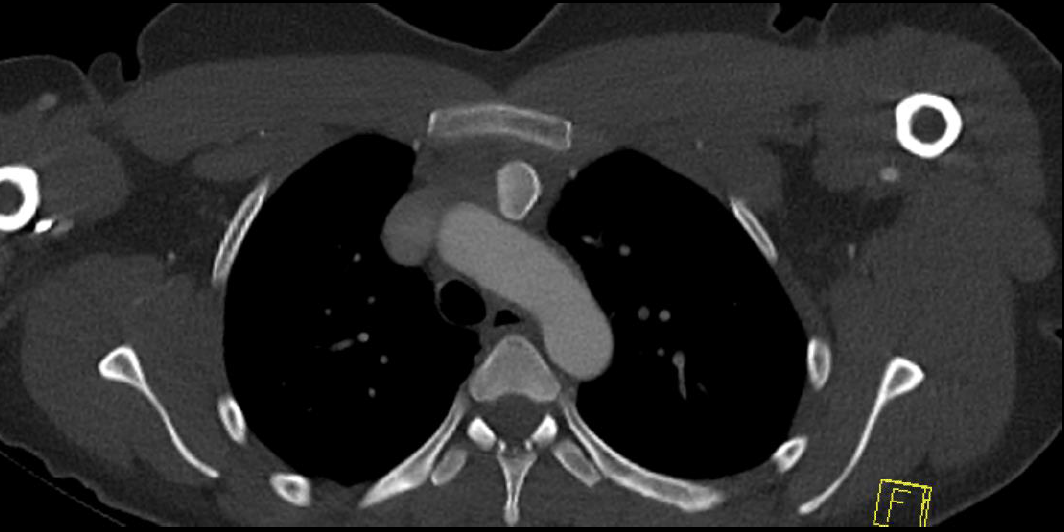

CT scan

Left posterior SCJ dislocation with pre- and post angiogram

Severe left posterior SCJ dislocation with subclavian vein compression